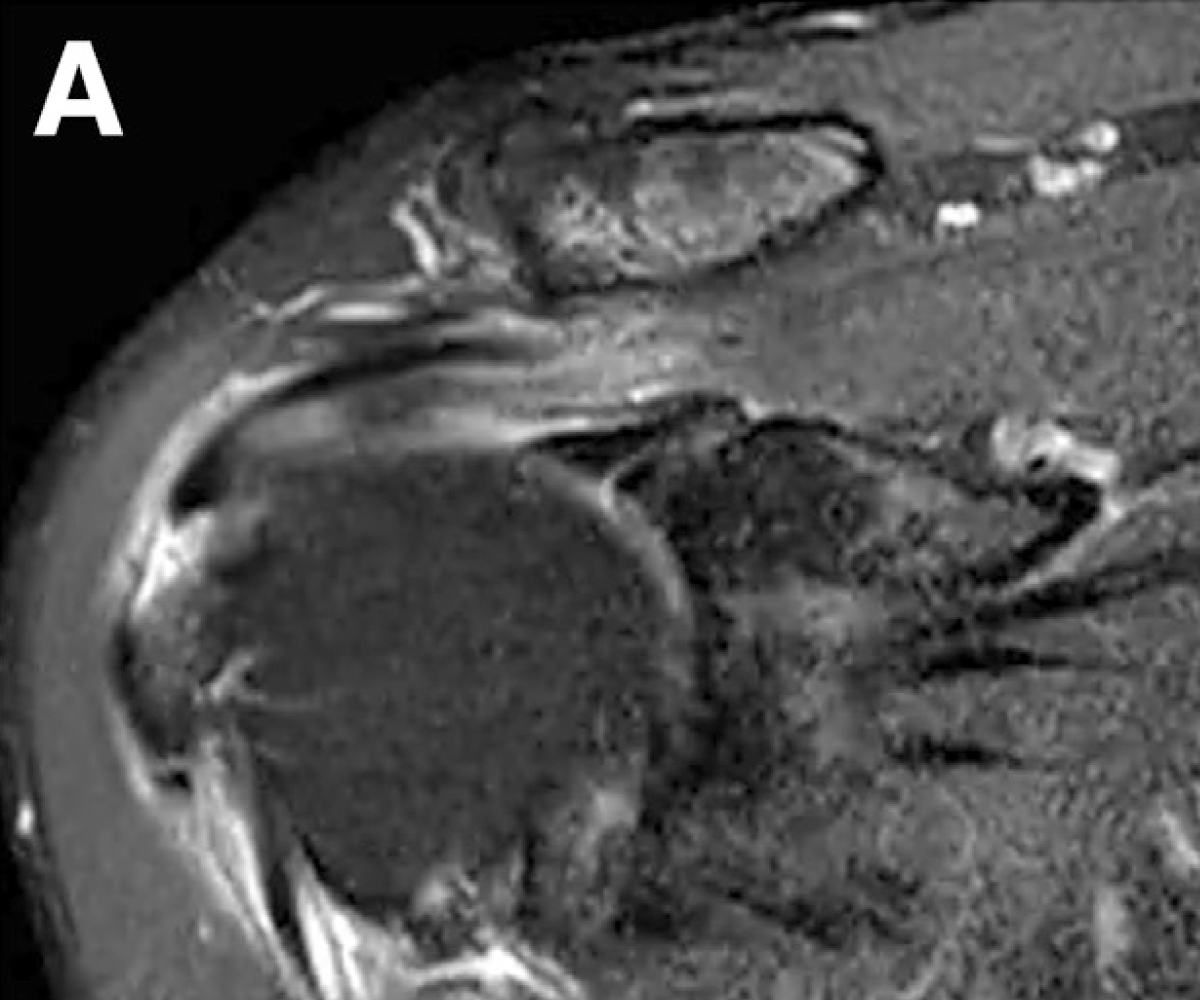

회전근개는 손상이 진행되면 부분파열이 되어 광범위 파열로 커질 수 있고,

옷감이 낡아 해지듯 힘줄도 점점 닳아 끊어지는 양상을 보입니다.

기존 봉합술은 “꿰매도 힘줄 자체가 얇고 약하면” 다시 버티기 어려울 수 있는데,

천을 덧대듯 패치를 덧대 보강해 더 굵고 단단한 힘줄로 만들어주는 것이 패치봉합술입니다.

리제네텐은 파열된 회전근개 부위에 콜라겐 패치를 덧대어

새로운 힘줄 조직 성장을 지원하고,

약 6개월 이내 점진적으로 흡수되며 새로운 조직층으로 바뀌는 방식입니다.